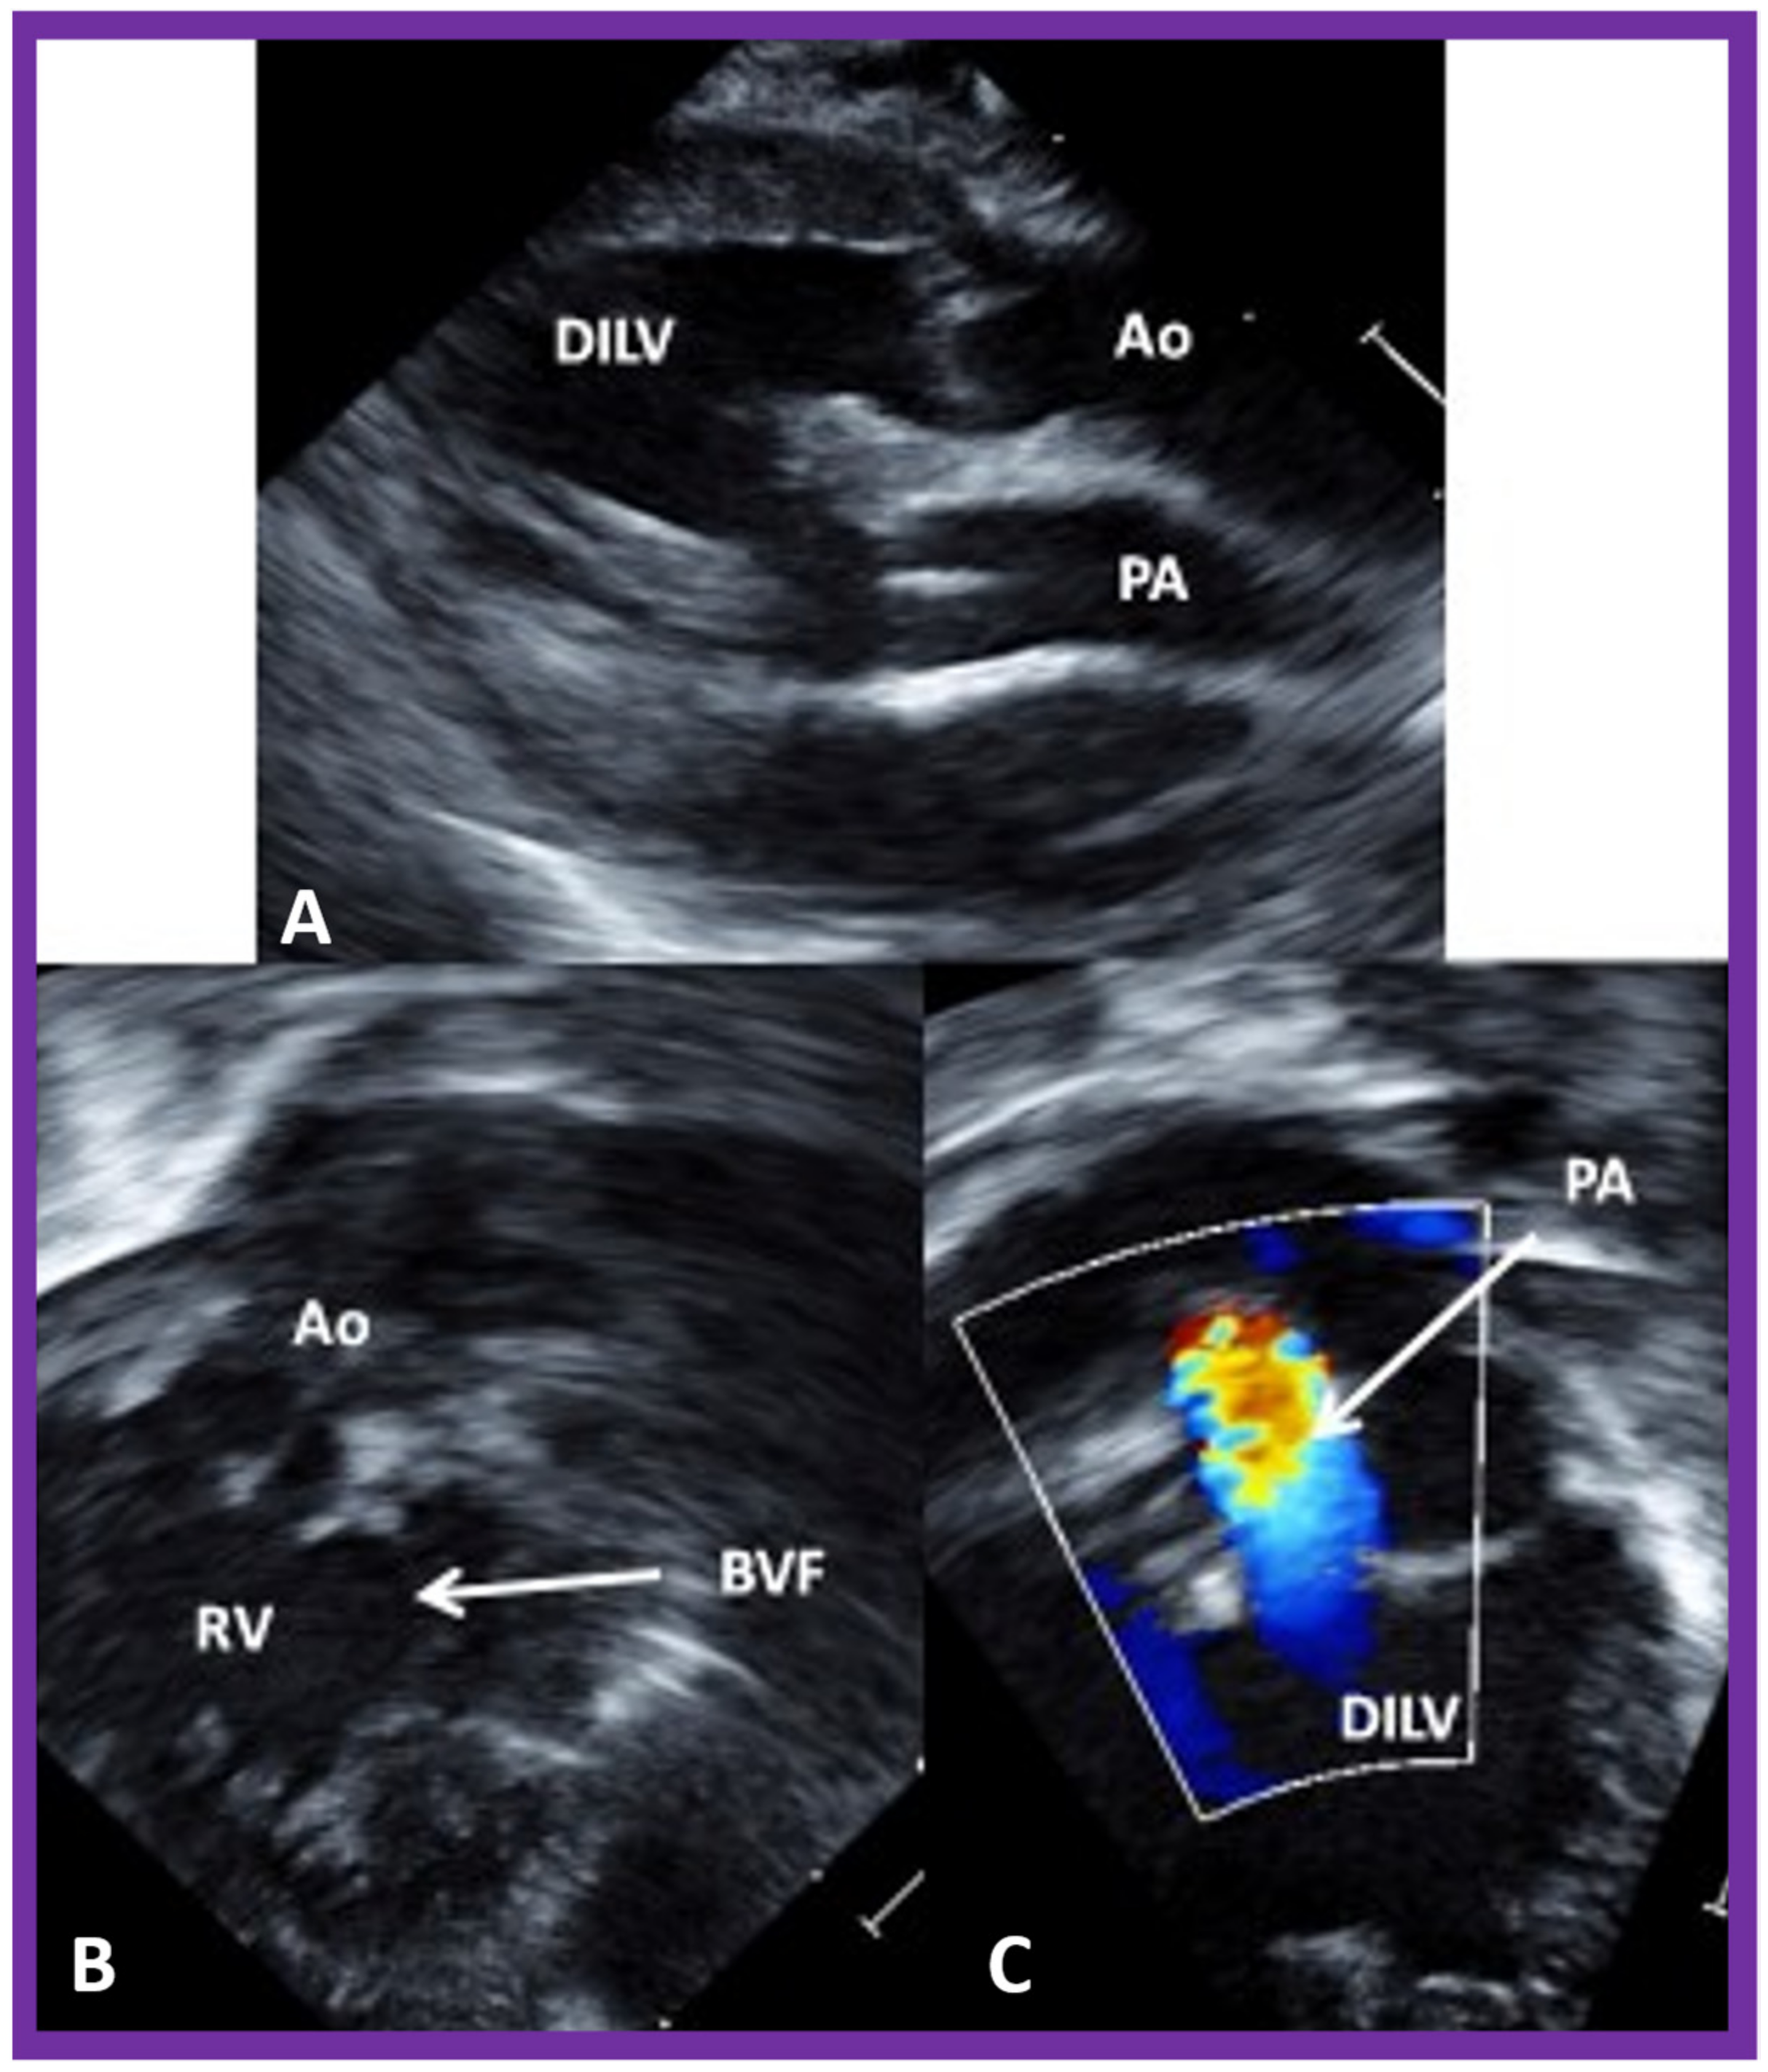

7. Echocardiogram